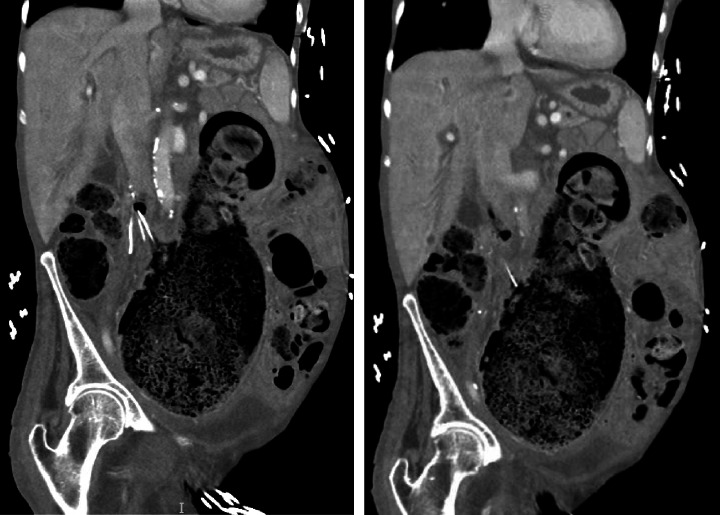

瘘管形成是解剖部位之间的连接,本质上是异常的。各种病因和相关结构存在这些异常发展。血管和肠系统之间的瘘管是罕见的。当存在时,解剖上的接近是决定涉及哪些结构的主要因素。主动脉肠瘘累及食道、十二指肠和小肠是众所周知的,胃也在罕见的情况下累及。瘘累及下腔静脉(IVC)和肠系统,也见过胃、小肠和胸内结肠介入手术后的瘘。我们报告了一位82岁的女性,她患有多种合并症,包括阿片类药物依赖、慢性便秘、下肢深静脉血栓形成、上消化道出血和下腔静脉滤器依赖,她出现了一个独特的问题。她的主诉是非特异性的,但最终诊断为下颌骨和乙状结肠之间的瘘管形成。本文所述的结肠瘘是文献中报道的第一例腹腔内瘘。

Fistula formation is a connection between anatomic locations that is intrinsically abnormal. A variety of causative etiologies and involved structures exist for these anomalous developments. Fistulas between vasculature and the enteric system are rare. When present, anatomical proximity is the dominant factor in determining which structures are involved. Aortoenteric fistulas involving the esophagus, duodenum, and small bowel are well-known with the stomach also being involved in rare instances. Fistulas involving the inferior vena cava (IVC) and enteric system have also been seen with the stomach, small bowel, and intrathoracic colon following an interposition each represented in reported cases. We present a case of an 82-year-old female with multiple medical comorbidities including opioid dependence, chronic constipation, recurrent lower extremity deep venous thrombosis, recurrent upper gastrointestinal (GI) bleeding, and IVC filter dependence who developed a unique problem. Her presenting complaints were nonspecific, but ultimately a diagnosis of fistula formation between the IVC and sigmoid colon was made. The colocaval fistula described here is the first intraperitoneal case to be reported in the body of literature.